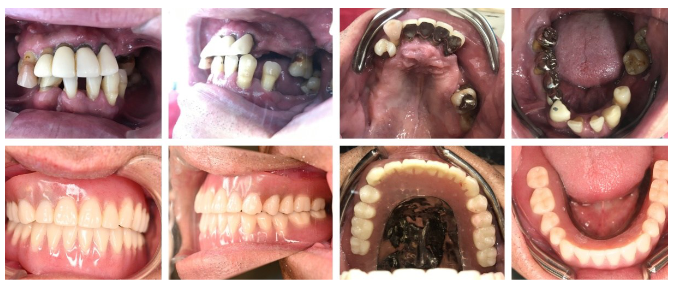

「グラグラしている歯があります。歯並びをきれいにし、しっかり噛めるようになりたい。」と、50代の男性Yさんが来院されした。お口の中を拝見すると、歯周病が重度に進行し、大きく動揺している歯が4本あり、満足に食事ができない深刻な状態でした。レントゲンで詳しく診断したところ、残すことが難しい歯が上4本、下3本あることが判明しました。

上段:治療前、下段:治療後、の写真です。

見た目も機能もきれいで健康的になり、大変喜んでいただけました!

治療後、Yさんは「なんでも思い通りに噛めるだけでなく、歯並びもきれいに仕上げてもらい大変満足しています。治療期間は長かったですが、マグネットにして本当に良かったです。これからは残っている歯を大切にしたいと思います。長い間ありがとうございました。」という感想を寄せてくださいました。マグネット式総入れ歯は、歯が少なくなり歯周病が進行している場合でも、残っている歯を有効に活用できる非常に優れた方法です。